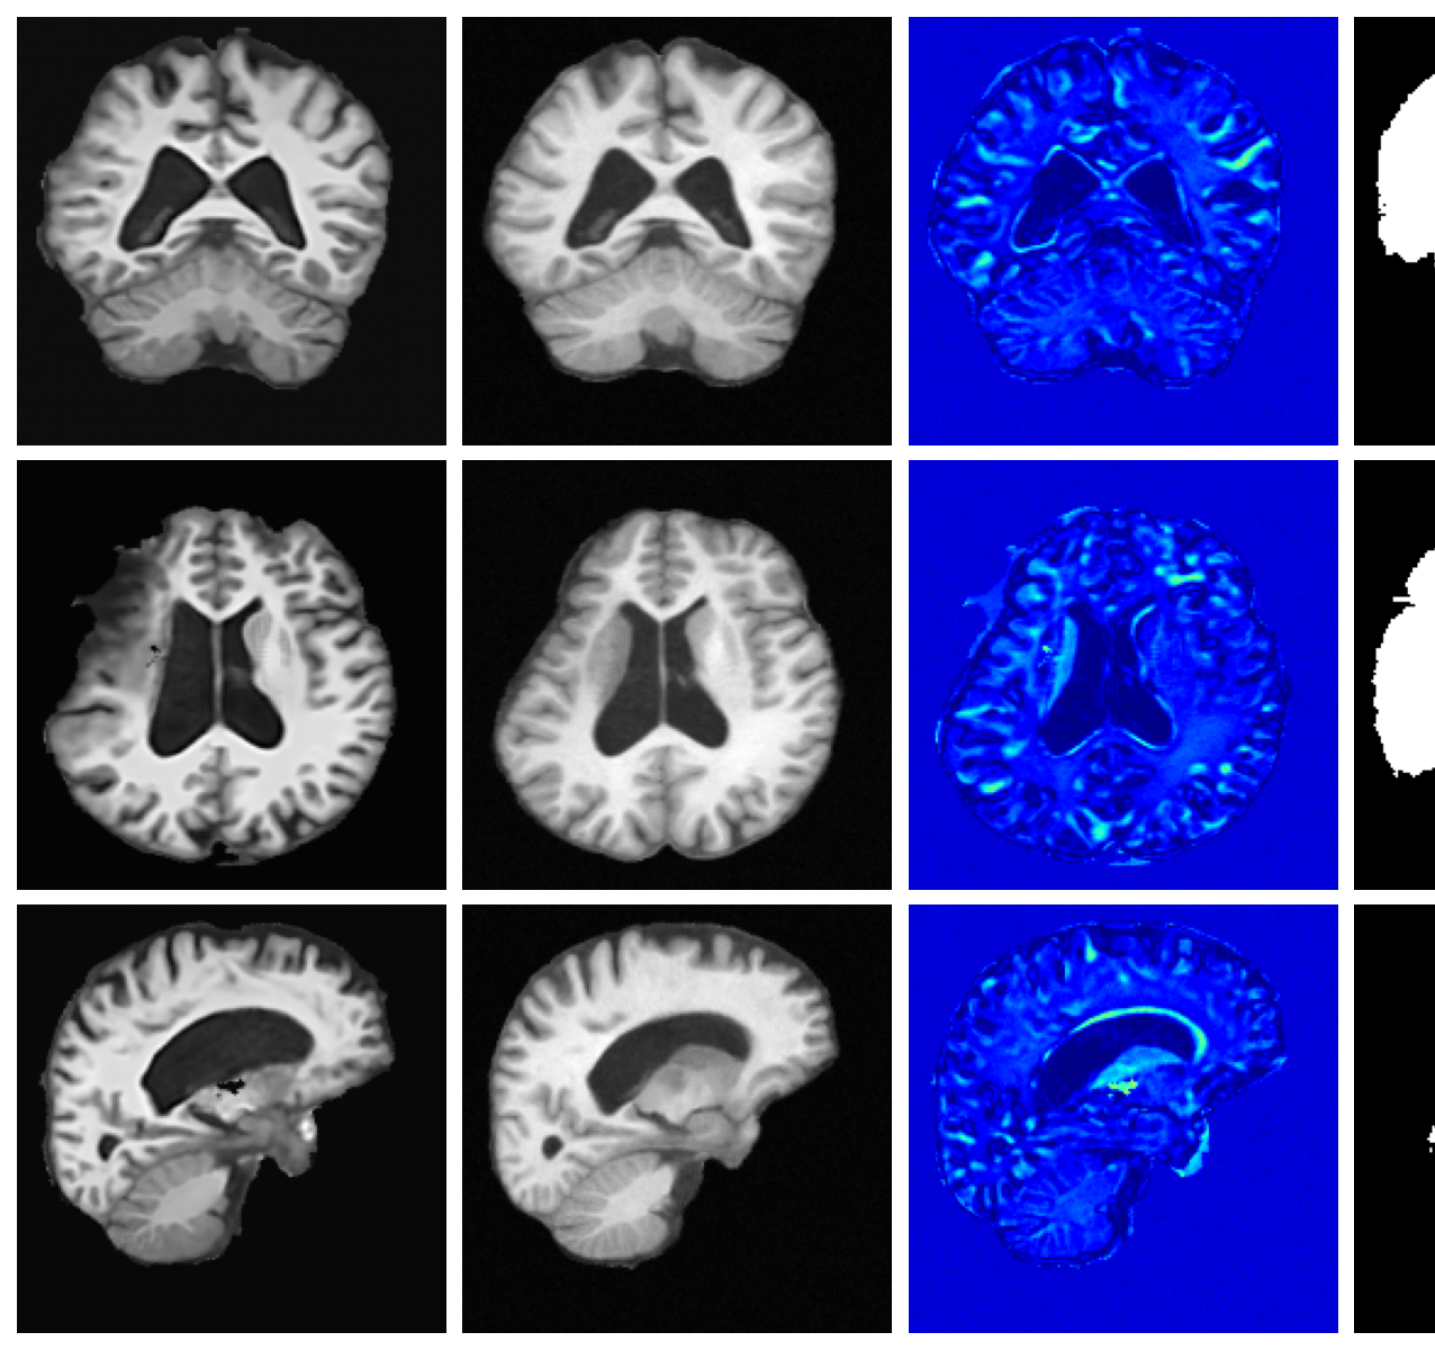

Qualitative T1w results are shown in Figure 2, with further examples for other modalities in Appendix A.8. LoHiResGAN and Res-SRDiff produce unrealistic images with severe artifacts, likely arising from bias fields, sharp intensity artifacts, and other noise not present during training. UniRes generates oversmoothed images, likely due to its TV prior and its reliance on information from multiple input modalities, whereas we apply it unimodally. Di-Fusion shows less pronounced but still notably blurry, voxelated reconstructions which lack the fine-grained details generate by our method. This is likely, in part, due to our use of synthetic rather than real noisy training data, which the method was designed for. As such data is scarce, and in our case unavailable, this requirement represents a significant limitation of Di-Fusion. SynthSR, whilst not as well as our method, does preserve key anatomical structures. However, our difference maps show reduced contrast, further supporting the strong quantitative results shown in Table 2.

IQM values comparing generated to ground-truth high-resolution scans are shown in Table 2. Our method outperforms baselines across several metrics, achieving the highest, or joint highest, rank for all datasets. Data-driven methods, LoHiResGAN, Res-SRDiff and Di-Fusion, fail to generalise to these cohorts, as illustrated by their poor performance. SynthSR, although outperforming competitively on some IQMs (and outperforming our method in VIF for T1w Clinical), is restricted to predicting T1w intensities. UniRes is often a close performing baseline, which is expected given that it also models image restoration explicitly with a forward model similar to ours. UniRes outperforms our method in some VIF values, whereas our method consistently achieves second best performance in this metric. For all other IQMs across all datasets, our method achieves the best performance, in some instances by quite considerable margins.

A.8 Additional qualitative restoration results

Additional qualitative results for the Clinical dataset are given in Figures 7, 8 and 9, and for the Low-field dataset in Figures 10 and 11.